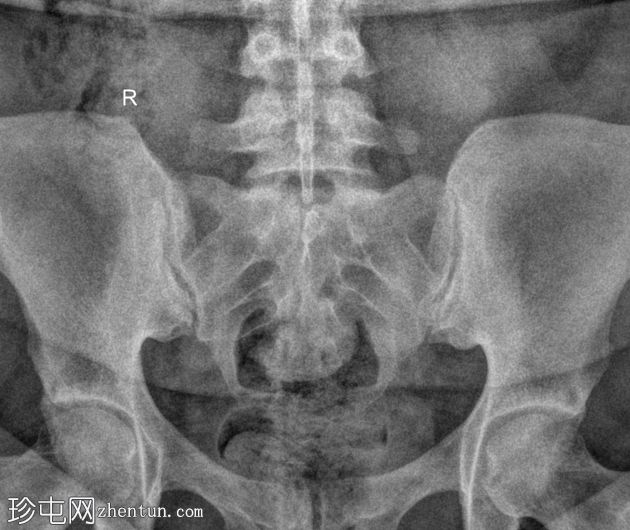

病例介绍

类

风湿

性关节炎伴腰痛。

患者资料

年龄:35岁

性别:女

斜位

正位

骶髂关节正位和斜位X线片显示正常。